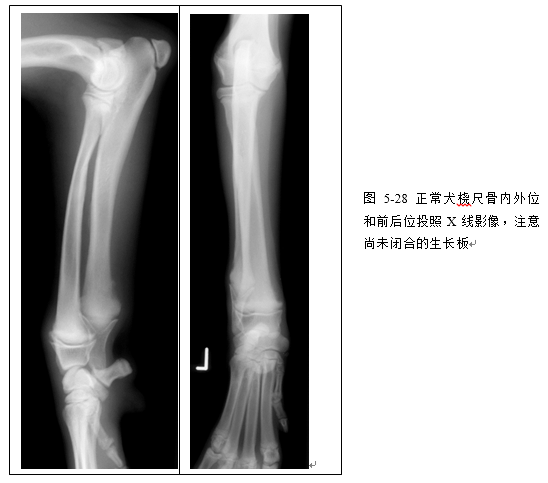

(2)识别桡尺骨、肱骨、肘关节、腕关节、肩关节X线影像(图5-28、5-29、5-30、5-31)。

(三)骺板(生长板)为位于骨骺和干骺端之间的软骨,X线片上显示为一低密度的带状阴影。骺板随年龄增长而闭合,但不同部位的骺板闭合时间不同。